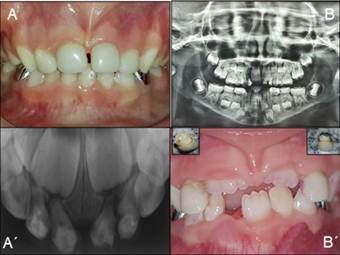

Clínicamente presentaba caries múltiples, fístulas en sector anterosuperior a nivel de 6.1, 6.2 y fractura amelodentinaria de 5.1. La radiografía revelaba ensanchamiento periodontal e imagen radiolúcida a nivel apical de 6.1, y pérdida de sustancia en 5.2, 5.1, 6.1, 6.2 (Figura 1).

Figura 1: Diagnóstico inicial